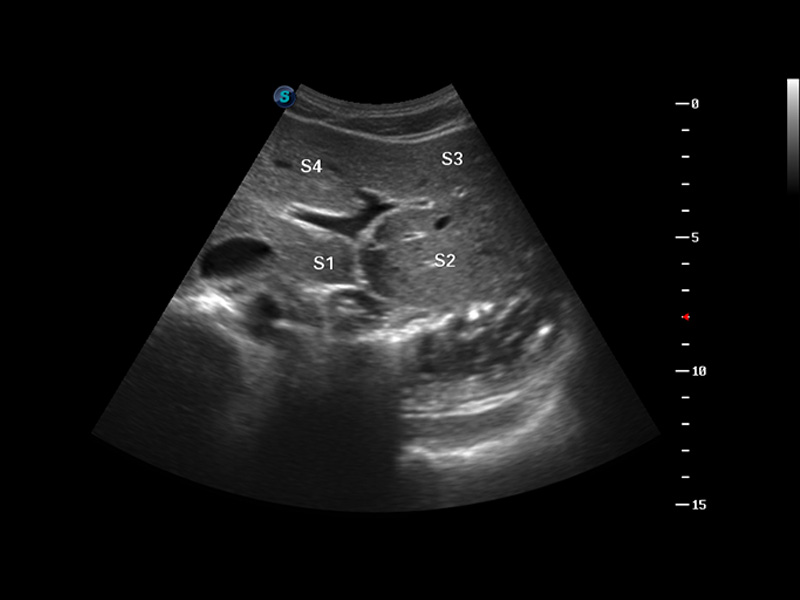

S8 EXP便攜式彩色多普勒超聲診斷儀是開立醫(yī)療研發(fā)的高端全身應(yīng)用型便攜彩超。高通道的VIS平臺(tái)融合可視化(Visual)、智能化(Intelligent)和人性化(Smart)的特點(diǎn),配以開立醫(yī)療自主研發(fā)生產(chǎn)的探頭大家族,使您能夠快速、準(zhǔn)確的獲得病人信息,提高工作效率的同時(shí)減輕疲勞。

成像技術(shù)

μ-Scan微米成像

諧波成像